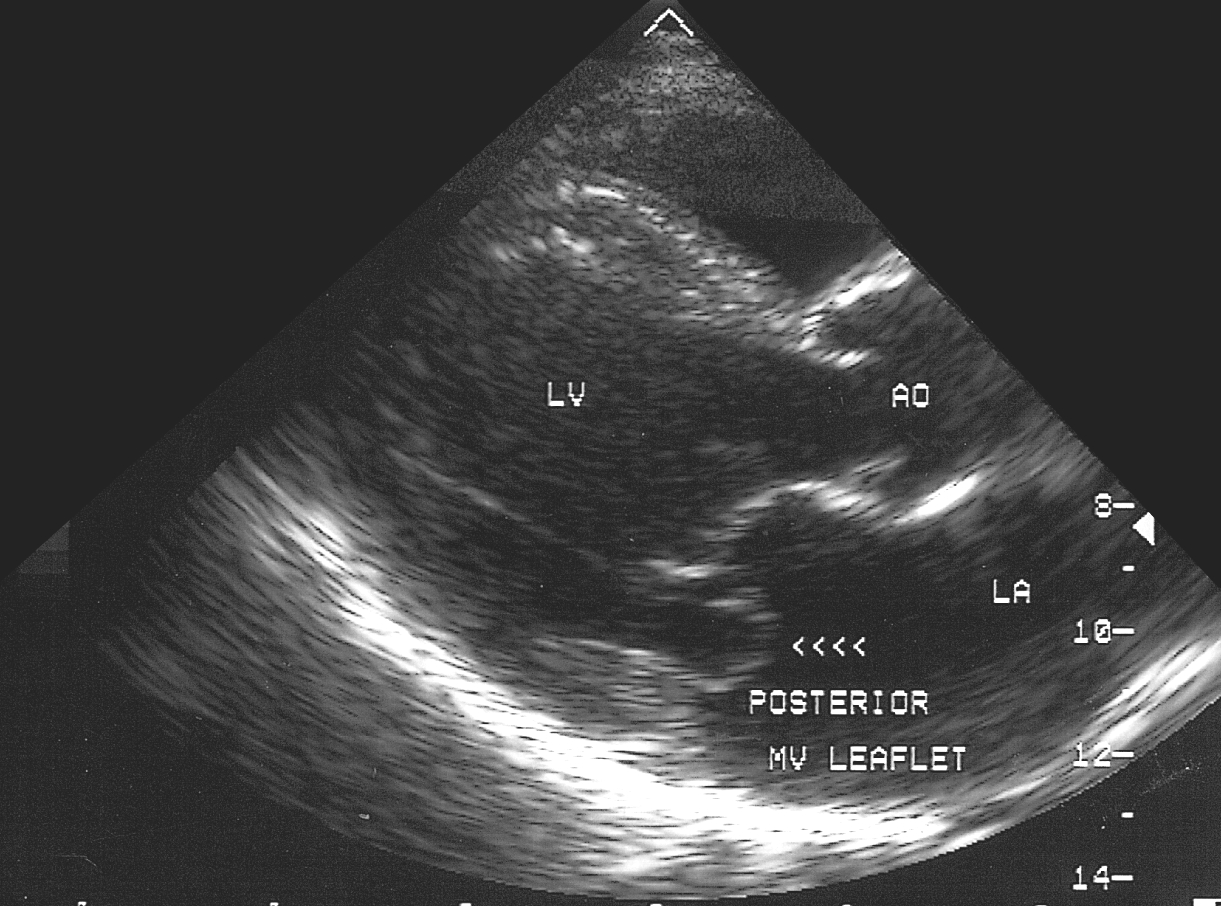

В диагностических целях врач собирает анамнез жизни и семейный анамнез, опрашивает больного. Назначаются лабораторные исследования: общий и биохимический анализ крови, общий анализ мочи. Из инструментальных методов: электрокардиография, рентгенография органов грудной клетки, эхокардиография. Однако наиболее эффективным методом выявления патологии является УЗИ сердца, позволяющее определить степень пролабирования створок и объем регургитации.